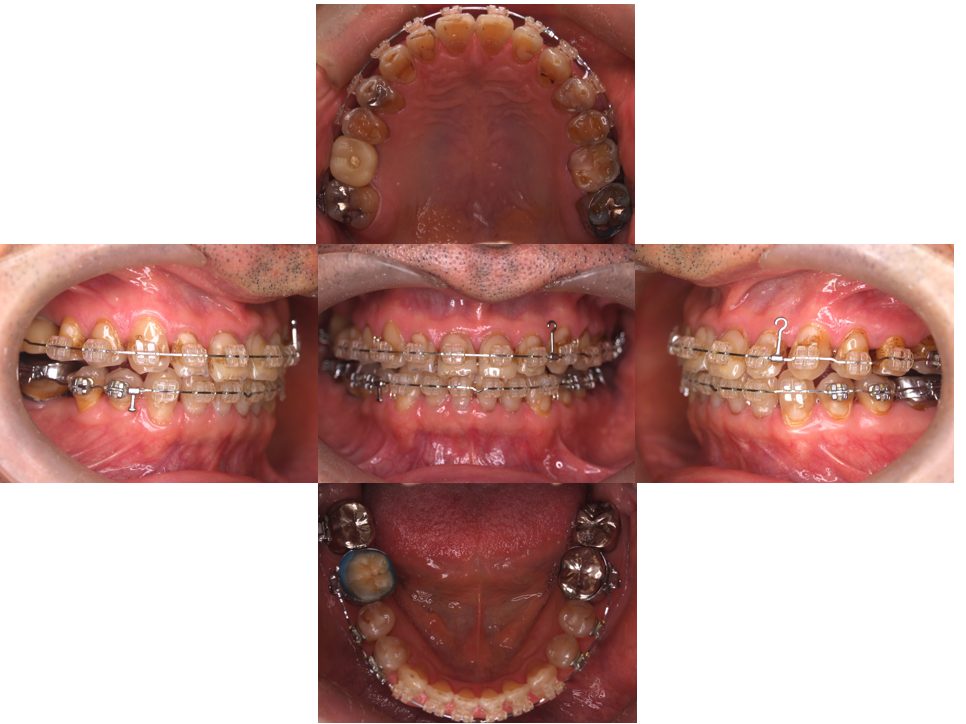

| 主訴 | 過去作成した右下の被せ物がずれて入っており、たまに腫れる。歯並びも気になる。 |

| 治療内容 | 矯正治療を行いました。 |

| 治療費 | 800,000円(税込み) |

| 治療期間 | 2年半(矯正治療期間 2年) |

| 治療回数 | 30回 |

| 想定されたリスク | 術前に基礎資料を整え分析し、セットアップモデル等でシミュレーションをしておかないと、予定通りの治療が行えないリスクがあった。 |